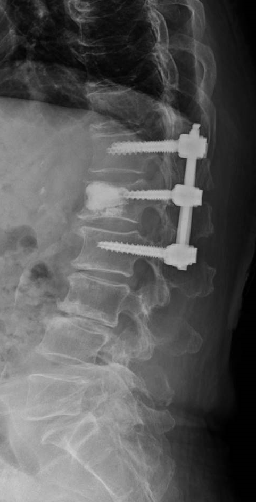

術前MRIでは腰椎正面で弯曲を認めています。多椎間の脊椎固定術を施行し症状が改善しています。

変性側弯症の患者さんで、難治性の腰痛と夜間も続く坐骨神経痛のために日常生活が困難でした。下位腰仙椎の多椎間で変性、側弯変形を認めます。

腰仙椎前方後方同時固定術による側弯変形の矯正、神経の除圧を行いました。悩んでいた腰痛がなくなり、坐骨神経痛が無くなったため夜間も穏やかに眠れるようになりました。